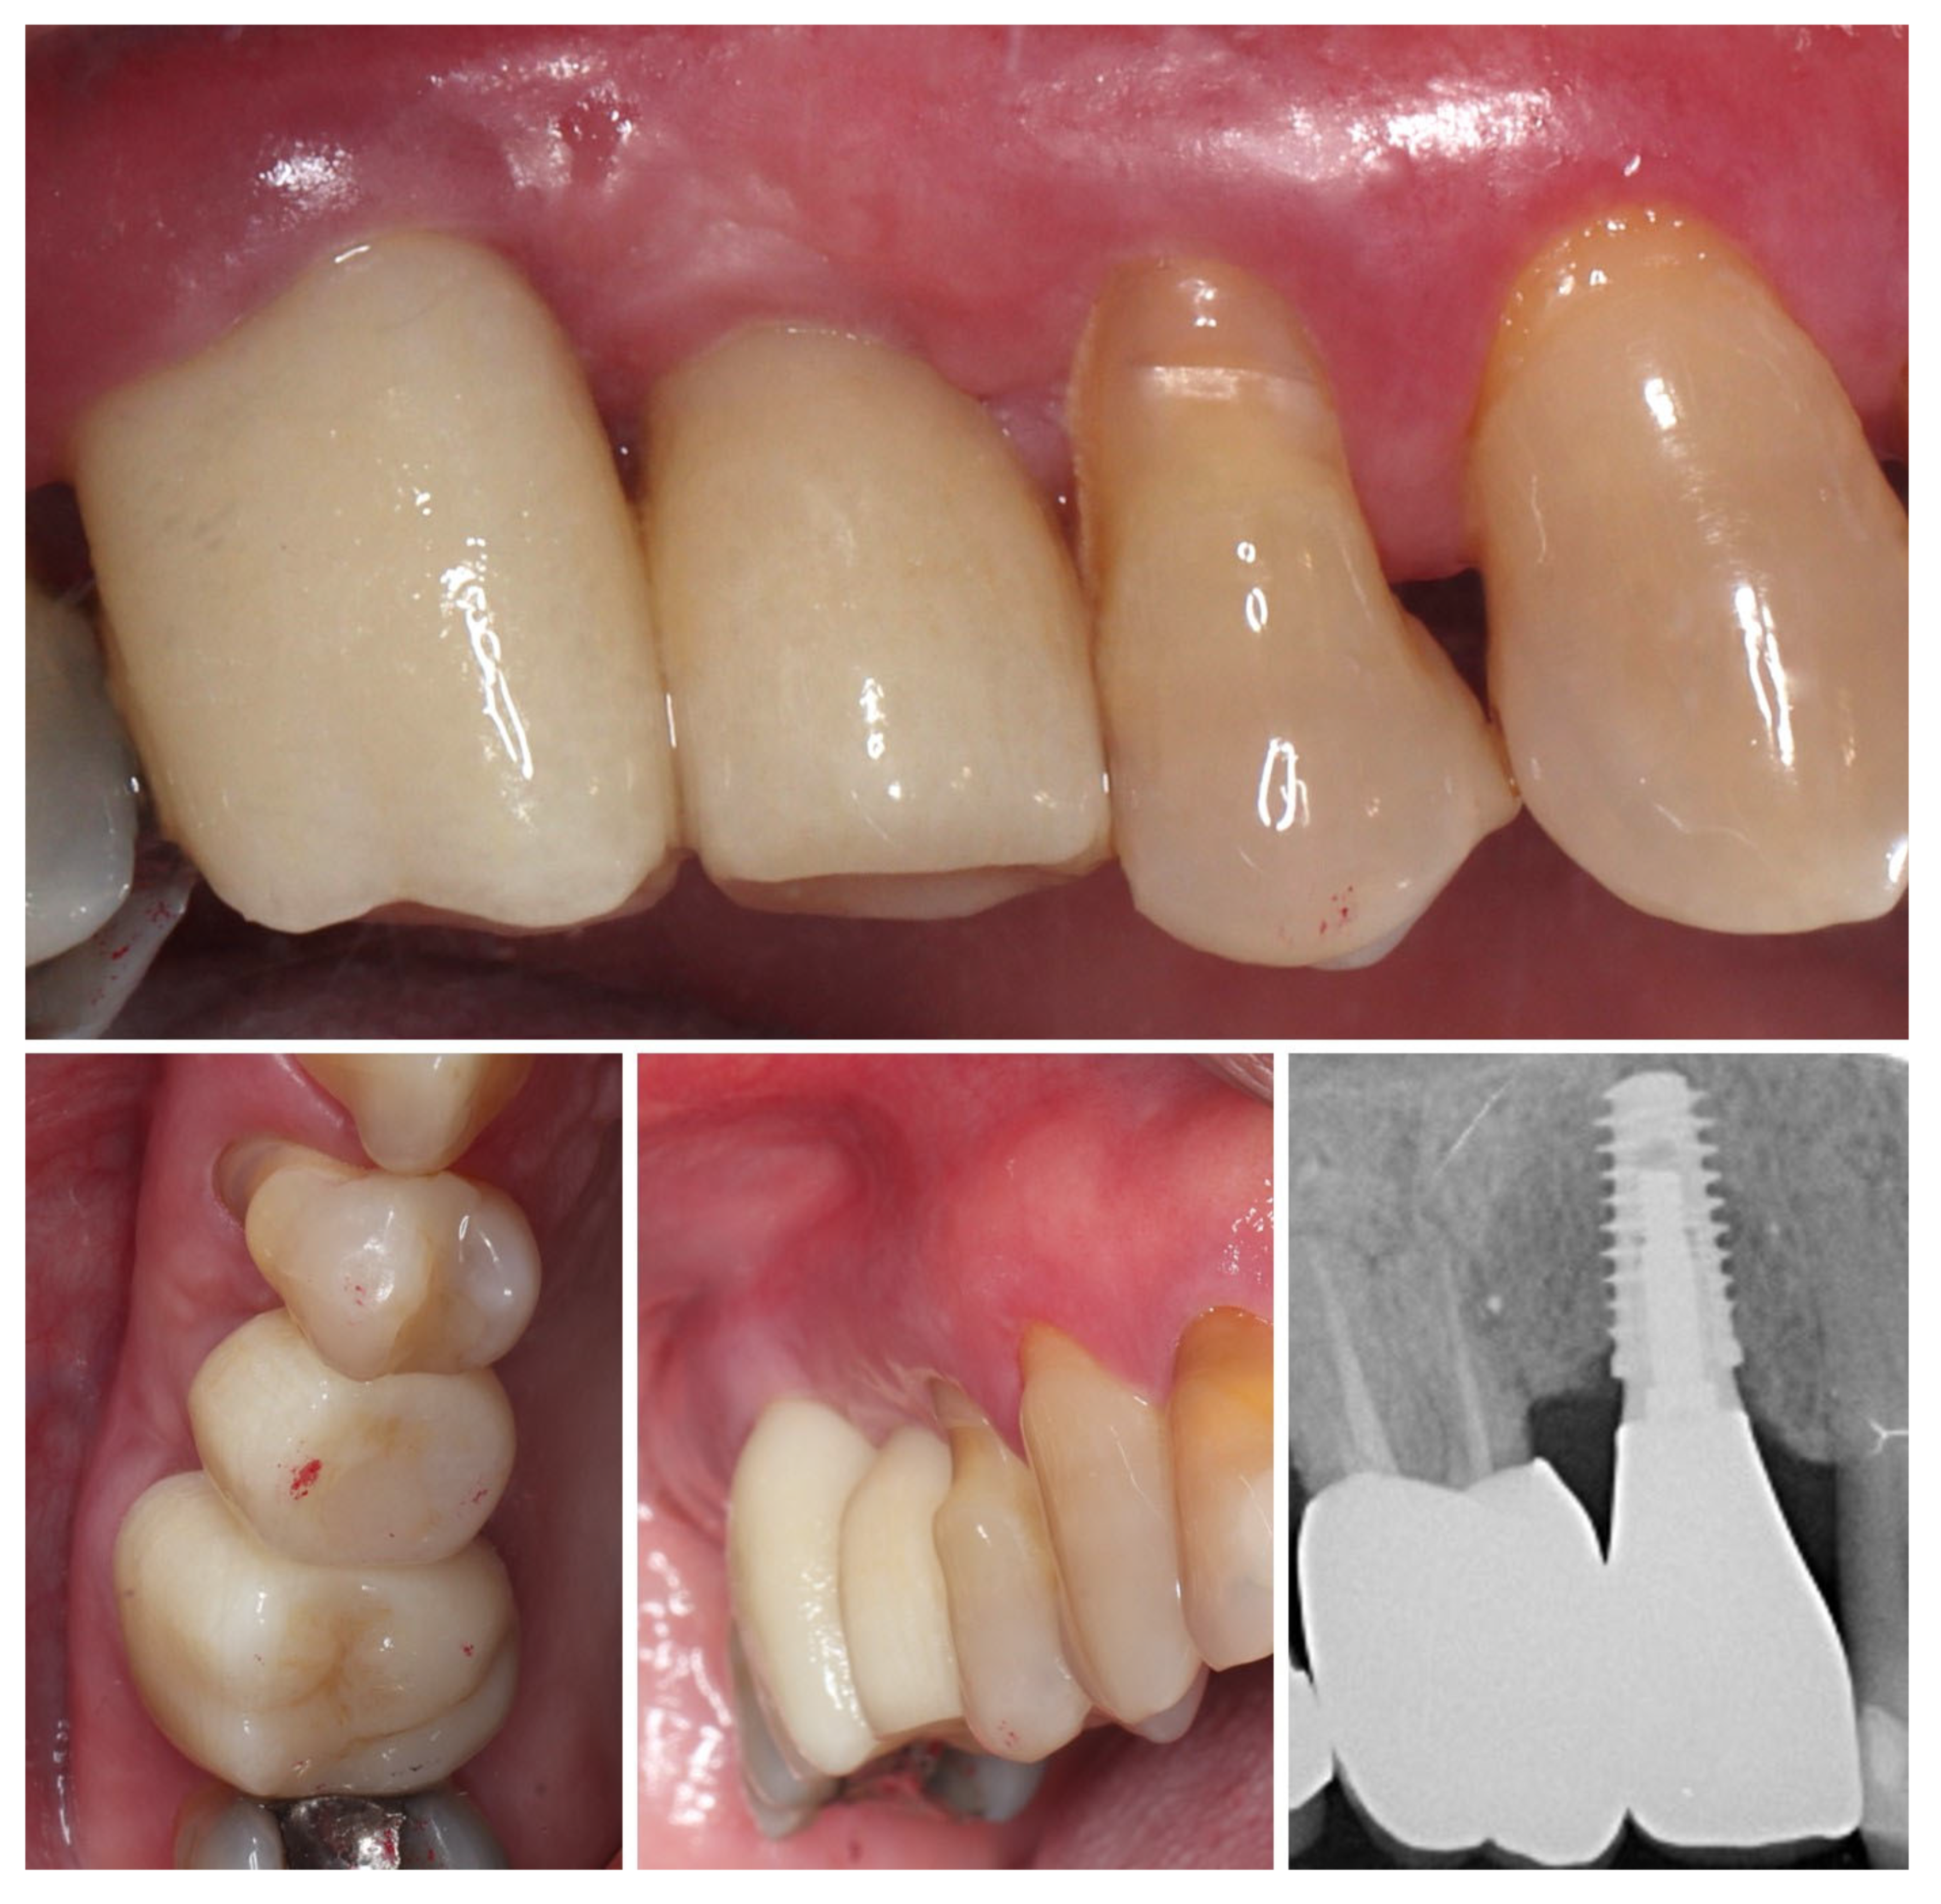

2. Materials and Methods—Clinical Case

| 5 | 8 months post-op (final crown) | 3.5 | 4.1 | Final crown placed, harmonious soft tissue contours, and stable crestal bone |

| 6 | 14 months post-definitive | Long-term stability of soft tissue and crestal bone confirmed |